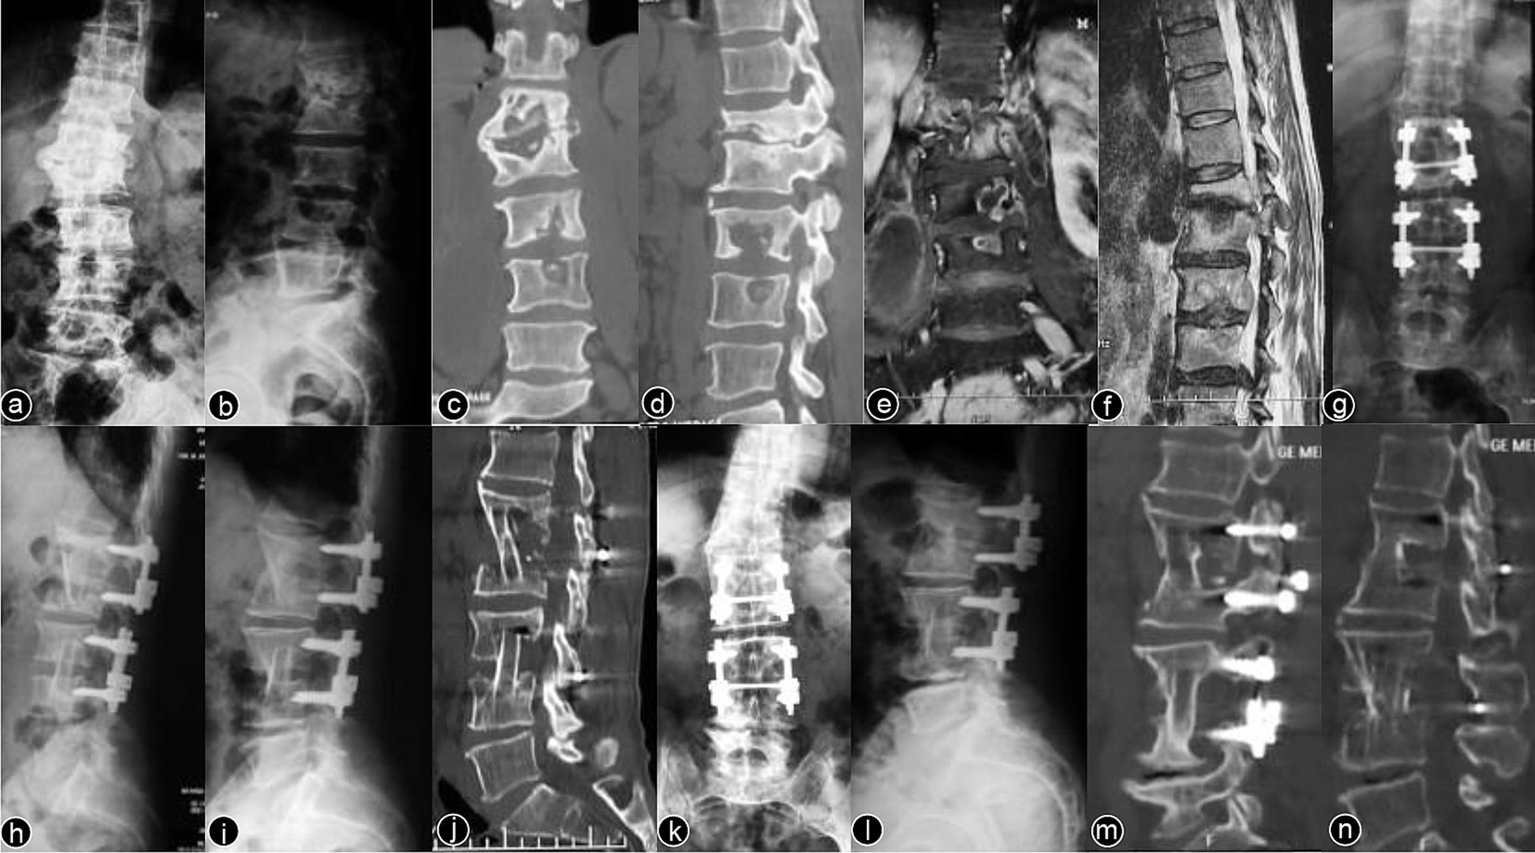

Typical cases are shown in Figures 26, with Figures 24 illustrating intervertebral fixation of the affected vertebrae in three patients from Group A, and Figures 5, 6 demonstrating non-intervertebral fixation in two patients from Group B.

Figure 2

www.frontiersin.org

Figure 2. Patient, male, 51 years old. Diagnosis: spinal tuberculosis (T6–T11). Surgical approach: intervertebral surgery. (A,B) Preoperative anteroposterior and lateral X-rays of the thoracic spine show roughened anterior margins of the T6–T11 vertebrae, narrowed intervertebral spaces, and kyphotic deformity. (C,D) Preoperative thoracic spine CT reveals narrowing of the intervertebral spaces, destruction of multiple vertebral bodies, paravertebral soft tissue swelling, and significant vertebral collapse with kyphotic deformity. (E) Preoperative thoracic spine MRI shows multiple abnormal vertebral signals, destruction of vertebral bodies and intervertebral spaces, and the formation of paravertebral abscesses. (F–I) Immediate postoperative anteroposterior and lateral X-rays, CT, and MRI of the thoracic spine show short-screw fixation at T7–T10, complete lesion removal, and satisfactory bone graft placement. (J) One-month postoperative lateral X-ray shows good internal fixation position with effective correction of the kyphotic deformity. (K–M) One-year postoperative lateral X-rays, CT, and 3D reconstruction show no loosening or breakage of the internal fixation, good bone graft positioning, and blurred bone graft interfaces, indicating healing.

Figure 3

Figure 3. Patient, male, 38 years old. Diagnosis: spinal tuberculosis (L1–L2/L3–L4). Surgical approach: intervertebral surgery. (A,B) Preoperative anteroposterior and lateral X-rays of the lumbar spine show roughened anterior margins of the L1–L4 vertebrae and narrowing of the intervertebral spaces. (C,D) Preoperative lumbar CT reveals narrowing of the L1–L2/L3–L4 intervertebral spaces, multiple non-contiguous vertebral body destruction, and scoliosis. (E,F) Preoperative lumbar MRI demonstrates narrowing of the L1–L2/L3–L4 intervertebral spaces, abnormal vertebral signals, and an epidural abscess occupying the spinal canal. (G,H) Immediate postoperative anteroposterior and lateral X-rays of the lumbar spine. (I,J) Two-year postoperative lateral X-rays and CT scans show stable internal fixation and well-healed bone grafts. (K–N) Ten-year postoperative anteroposterior and lateral X-rays and CT scans confirm no loosening or breakage of the internal fixation, with solid bone graft fusion and no recurrence of the local lesion.